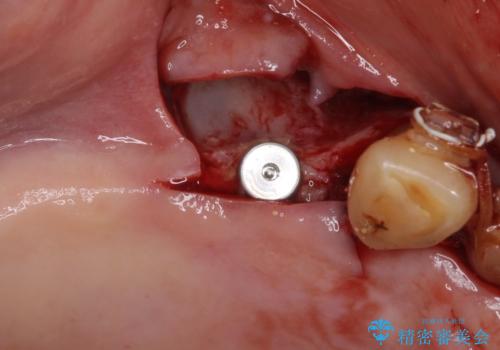

前歯部については抜歯が必要な歯を抜歯し、インプラントやブリッジなどにより補綴治療を行うこととしました。

臼歯部は今後抜歯が必要となった際に、インプラントにより咬合を構築していくこととしました。今回の治療においても、今後の臼歯部の治療に対応できるよう治療計画を立案しています。